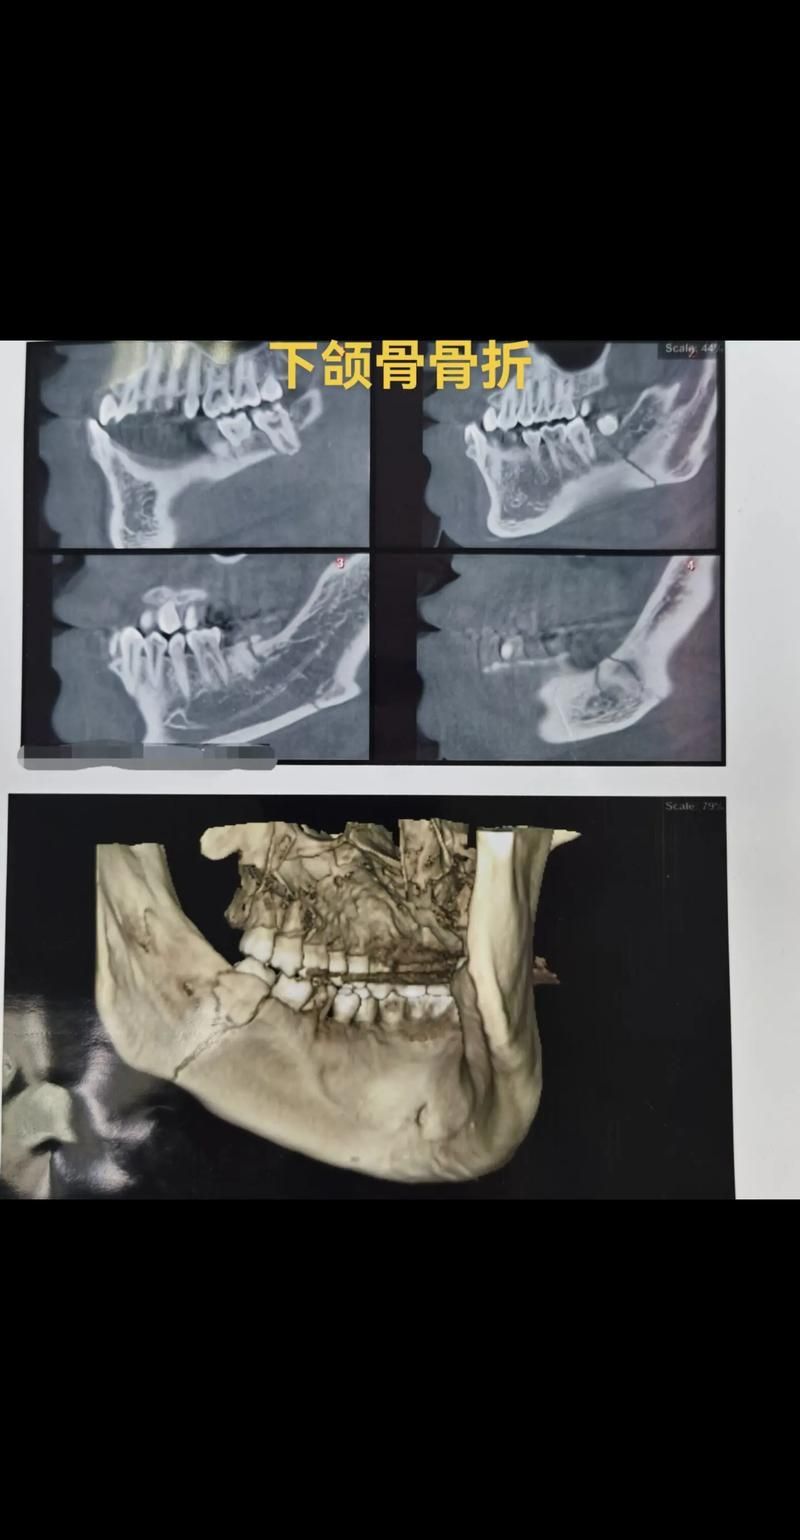

龍魚百科 如何判斷龍魚下頜是否骨折?(如何判斷龍魚(arowana)下頜是否骨折) 魚(Arowana)下頜骨折的診斷通常需要專業(yè)的獸醫(yī)進(jìn)行,以下是一些可能用于判斷龍魚下頜是否骨折的步驟和指標(biāo):,1.觀察外觀:檢查龍魚的口腔和下頜區(qū)域是否有腫脹、淤血或異常的顏色變化。,2.觸摸檢查:輕輕觸摸下頜... 2026-02-19 8 閱讀 7 評(píng)論 楊凌魚缸定做

如何判斷龍魚下頜是否骨折?(真實(shí)龍魚下頜骨折的診斷通常需要專業(yè)的獸醫(yī)雖非直接對(duì)比圖)) 魚下頜骨折的診斷通常需要專業(yè)的獸醫(yī)進(jìn)行,以下是一些可能表明龍魚下頜骨折的跡象:,1.**外觀檢查**:仔細(xì)觀察龍魚的口腔和下頜區(qū)域,骨折可能導(dǎo)致下頜骨變形、腫脹或顏色改變。,2.**行為觀察**:如果龍魚表現(xiàn)... 2026-02-13 8 閱讀 7 評(píng)論 淮北花鳥魚蟲市場(chǎng) 龍魚百科